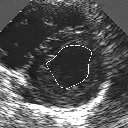

DETECTION AND TRACKING OF ANATOMICAL STRUCTURES USING DEFORMABLE TEMPLATES AND A NOISE MODEL ESTIMATION IN AN ECHOGRAPHIC SEQUENCE

In this work, we present a new method to shape-based segmentation of deformable anatomical structures in medical images and validate this approach by detecting and tracking the endocardial border in an echographic image sequence. To this end, a global prior knowledge of the endocardial contour is captured by a prototype template with a set of admissible deformations to take into account its inherent natural variability over time. In this approach, the data likelihood model rely on an accurate statistical modeling of the grey level distribution of each class present in the image. The parameters of this distribution mixture are given by a preliminary estimation step which takes into account the distribution shape of each class. Then the tracking problem is stated in a Bayesian framework where it ends up as an optimization problem. This one is then efficiently solved by a genetic algorithm combined with a steepest ascent procedure. This technique has been successfully applied on synthetic images and on a real echocardiographic image sequence. This method seems to be particularly well suited to handle ultrasound images with strong speckle noise on which edge information cannot be exploited. Finally, the local and global minimization procedure we propose is fast, robust and do not require initialization of the template close to the desired solution. Initialization may be defined at random, leading to segmentation and tracking procedure that are completely data driven. (slides)

Figure 1:   Tracking of the endocardial contour in a medical echographic sequence at different time frames during the cardiac cycle. From top left to bottom right : frame 1, 4, 6, 9, 12, 13, 18, 20, 27, 30, 35, 40, 41, 44, 46.